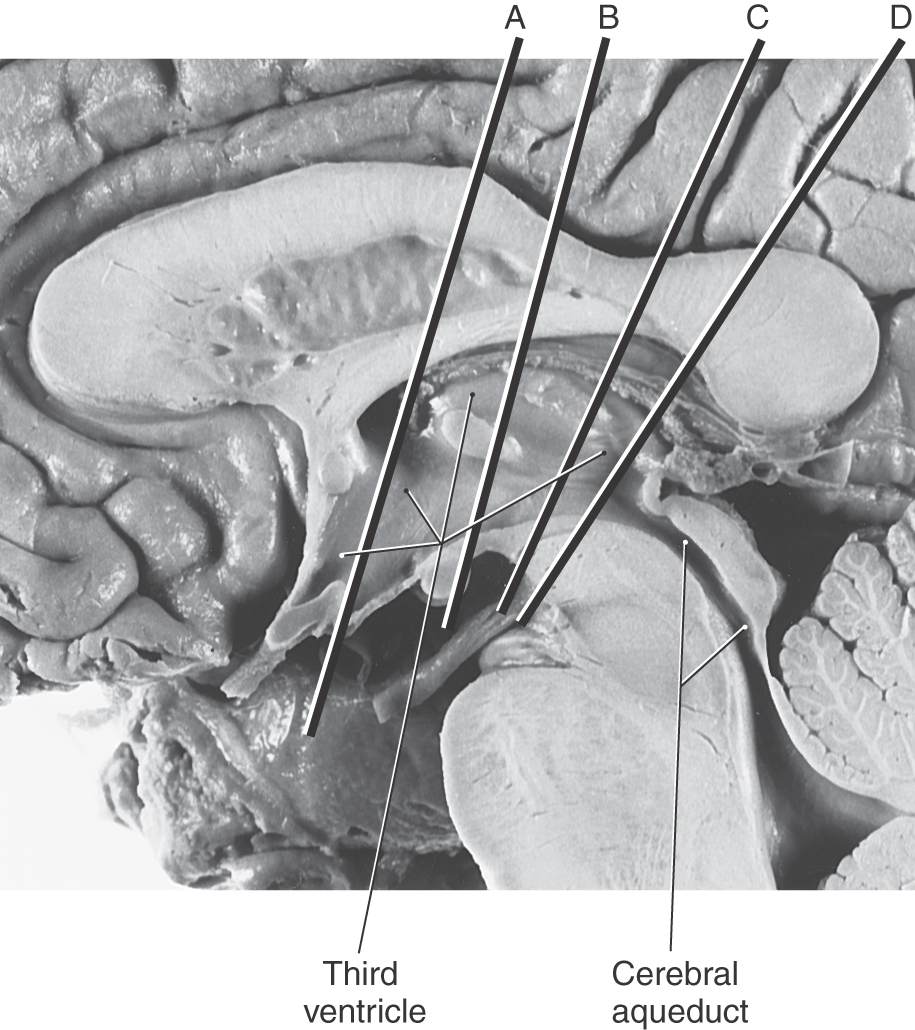

The cavity of the diencephalon, the third ventricle, is a narrow, vertically oriented midline space located between the paired dorsal thalami and hypothalami of the two sides (Figs. 15-6 and 15-7). In addition to its connections with the lateral ventricles and the cerebral aqueduct, the third ventricle has small evaginations or recesses associated with the optic chiasm (supraoptic recess), the infundibulum (infundibular recess), and the pineal gland (pineal and suprapineal recesses) (Figs. 15-1 and 15-4).

Figure 15-6. Midsagittal view of the diencephalon. This view correlates with the drawing in Figure 15-3. Lines A through D indicate the planes of the stained sections in Figure 15-7.

Figure 15-7. Four levels of the forebrain from rostral (A) to caudal (D) showing the internal structure of the hemisphere with emphasis on the diencephalon. These levels correlate with those shown in Figure 15-6 and with the planes represented in the exploded view in Figure 15-10. Weil stain.

All four diencephalic subdivisions can be approximated in a midsagittal section of the forebrain (Figs. 15-4 and 15-6). The dorsal thalamus is located superior to the hypothalamic sulcus and extends from the interventricular foramen caudally to the level of the splenium of the corpus callosum. The hypothalamus lies inferior to the hypothalamic sulcus and is bordered rostrally by the lamina terminalis and caudally by a line that extends from the posterior aspect of the mammillary body superiorly to intersect with the hypothalamic sulcus. The only diencephalic structures visible on the inferior surface of the hemisphere are those related to the hypothalamus, including the optic chiasm, infundibulum, medial and lateral eminences, and mammillary bodies (Fig. 15-5). The ventral thalamus (subthalamus) does not border on the ventricle; rather, it occupies a position caudal to the hypothalamus, rostral to the diencephalon-midbrain junction, and lateral to the midline (Figs. 15-4 and 15-7B). Epithalamic structures are located posteriorly and caudally, in close apposition to the posterior commissure, and include the pineal gland, the habenular nuclei, and the main afferent bundle of these nuclei, the stria medullaris thalami.